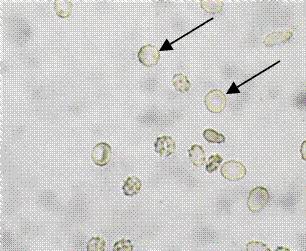

4、箭头所指细胞内结构的名称:红细胞

9、箭头所指细胞内结构的名称:草酸钙结晶